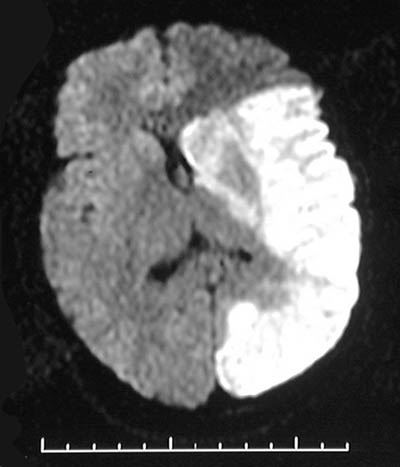

| The MRI scan in FLAIR mode above and enhanced below reveals an area of massive infarction of the left cerebral hemisphere, mostly in the right middle cerebral distribution, that is of recent formation, with brain swelling and a midline shift to the right compressing the ventricular system. |